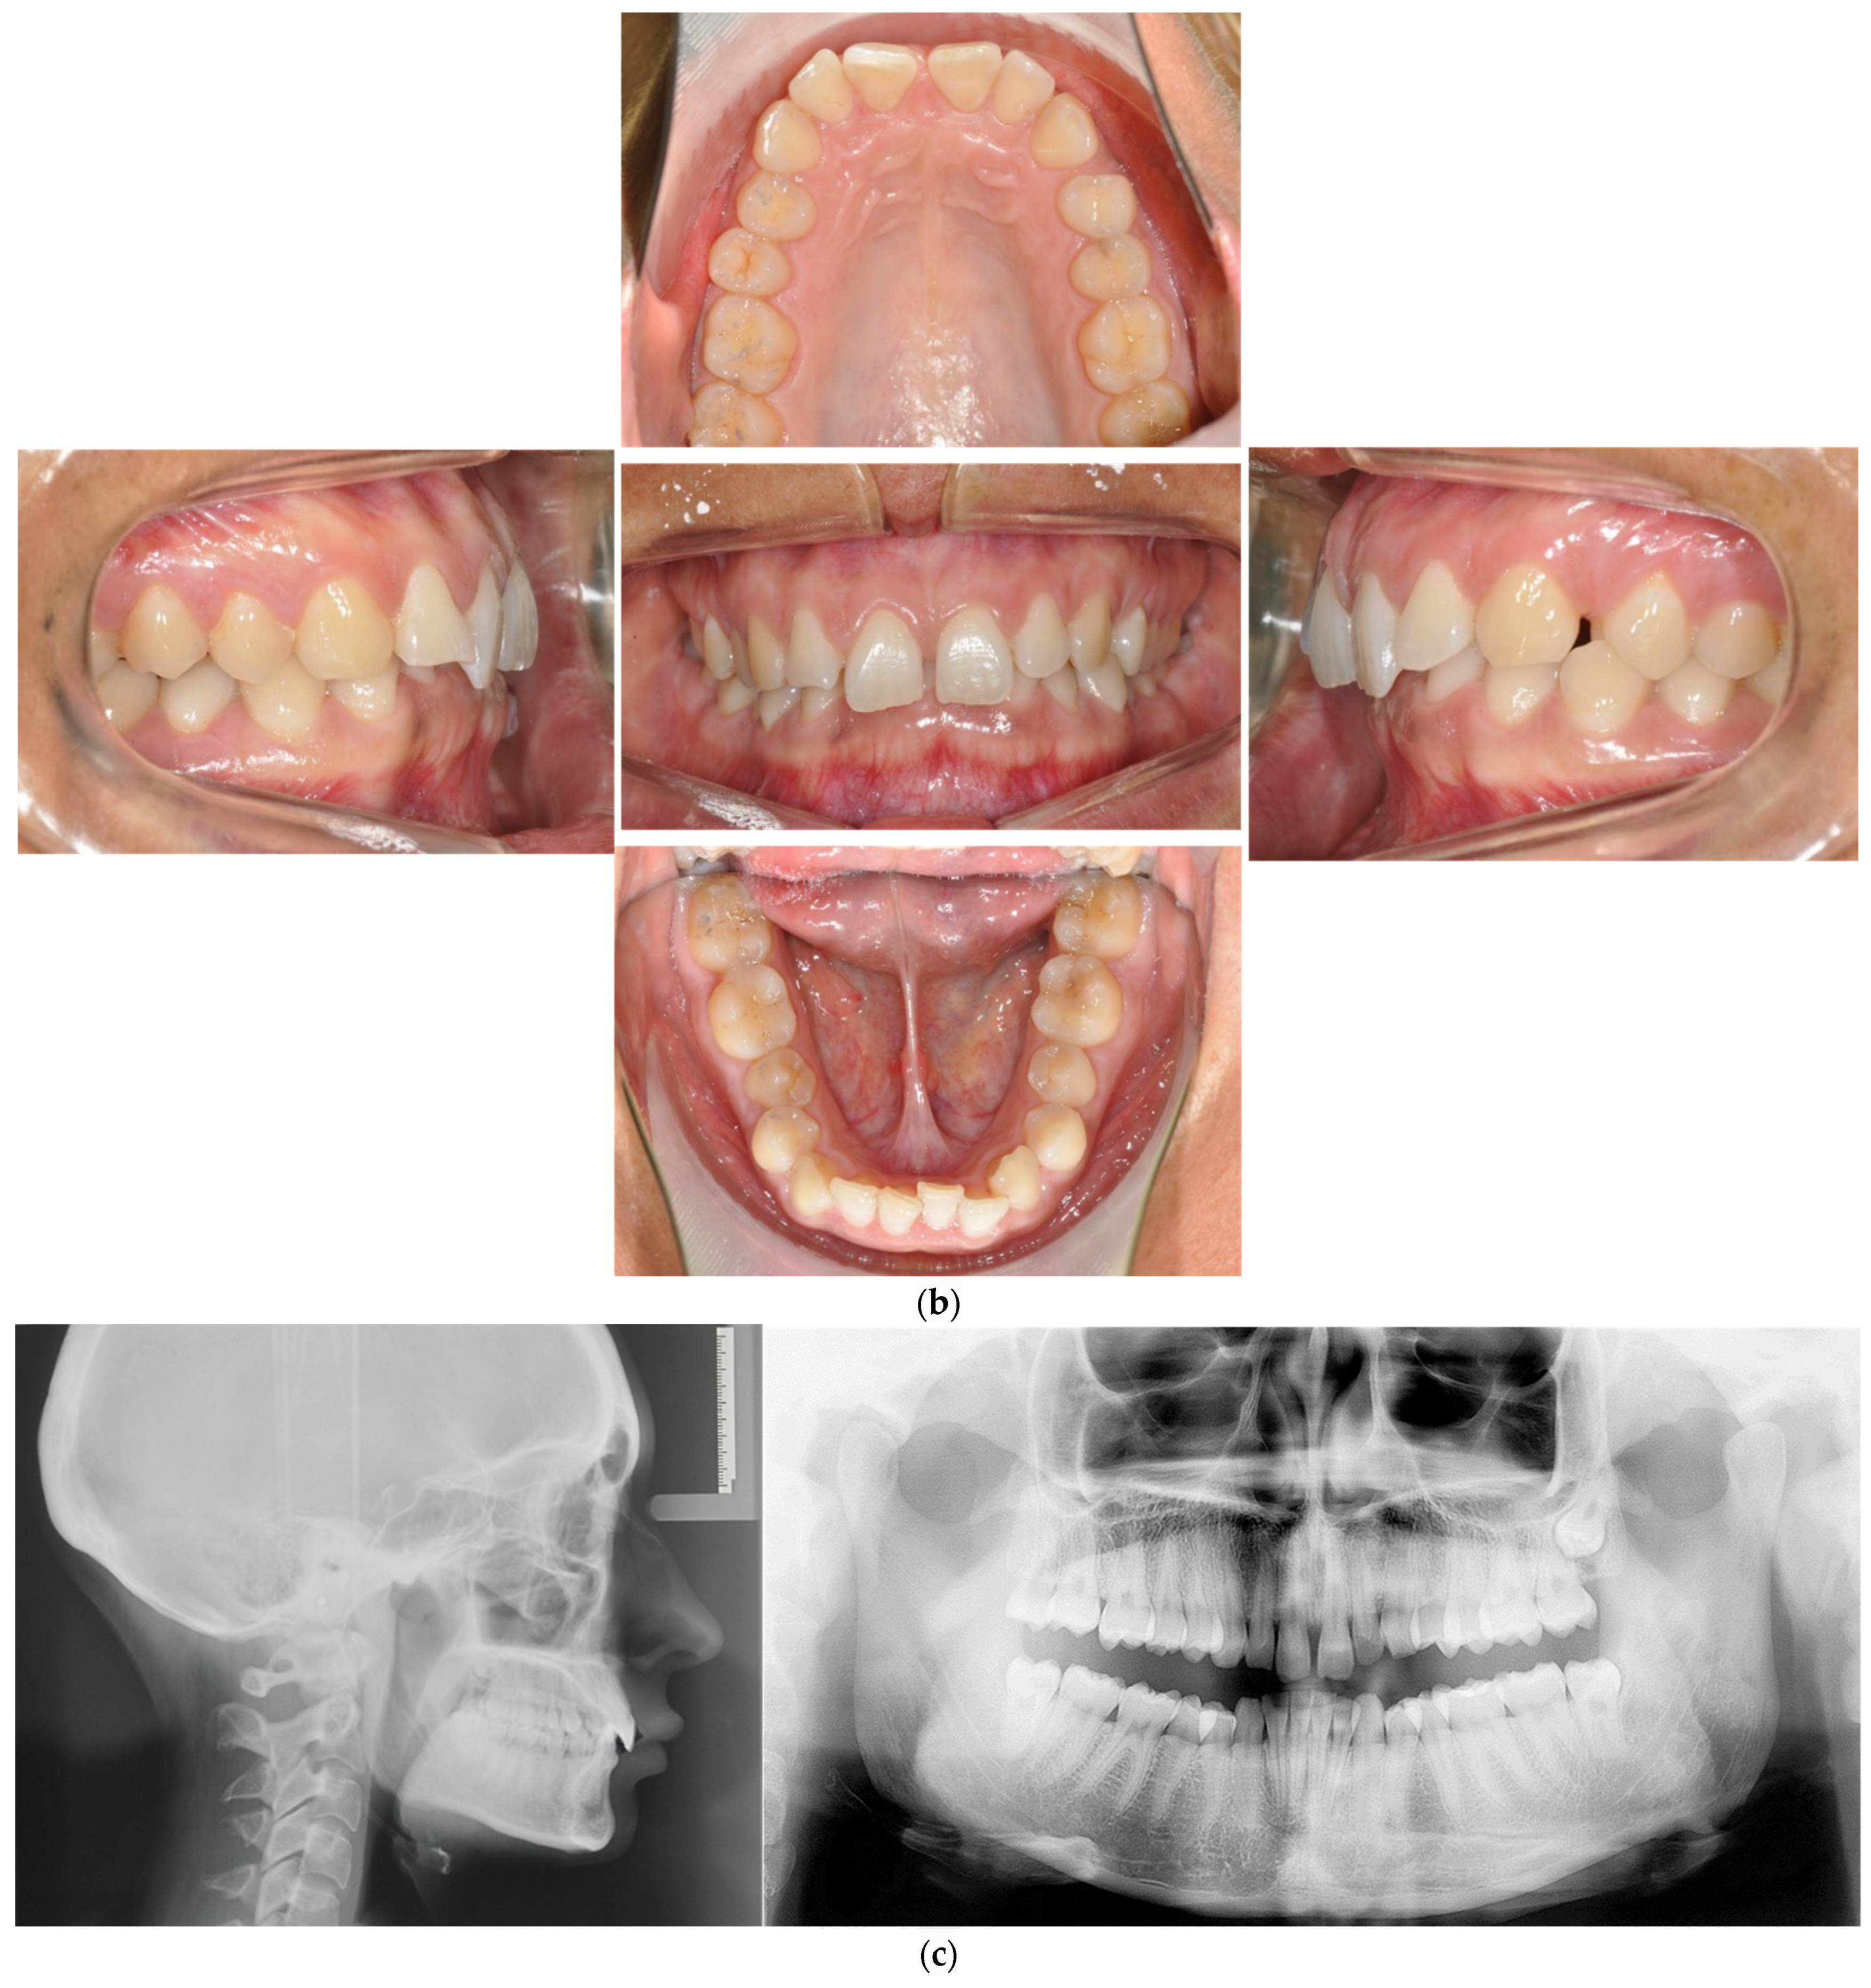

The patient was a 30-year-old female seeking orthodontic treatment for aesthetic reasons. She was unhappy with the position of her upper anterior teeth. Upon extraoral examination, she presented a harmonious profile with adequate lip closure but reduced lower facial height and deep mento–labial sulcus. Intraoral examination revealed retroclination of the upper incisors and an Angle Class I occlusal relationship at the right and left molars but a half-distal relationship on the left side, with deviation of the upper midline towards the left. She also presented a deep bite without palatal impingement and slight crowding in the lower arch. Both arches were U-shaped, with normal gingival biotypes. All teeth were present (Figure 3).

Figure 3.

(a–c) The initial profile and frontal smile view and intraoral images and radiographs, including panoramic radiographs and lateral cephalograms. (d) The digital setup performed for the treatment. (e) The treatment in progress with aligners and lingual appliances. (f–h) Post-treatment images and a comparison with the initial images. (i) A superimposition of the pre- and post-treatment cephalograms.

The treatment plan chosen in this case was a hybrid approach involving combined upper aligners and a lower lingual appliance, followed by upper lingual appliances. The aims were to resolve the deep bite and Class II canine relationship, achieving Class I canine and molar relationships while preserving the facial profile.

To correct the rotations in the upper arch, a series of twelve aligners associated with bite ramps were used before bonding the lingual appliance. Simultaneously, the Alias PSL lingual system was used in the lower arch with the following archwire sequence: 0.013- and 0.016-inch CuNiti for levelling and alignment; 0.016 × 0.016-inch and 0.018 × 0.018-inch CuNiTi for rotational, tip and torque control; and 0.0175 × 0.0175-inch TMA (titanium–molybdenum alloy) for detailing.

In the second phase, the upper arch was also bonded with Alias lingual brackets that were threaded with the following archwire sequence: 0.014- and 0.016-inch CuNiti for levelling and alignment; 0.016 × 0.016-inch and 0.018 × 0.018-inch CuNiTi for rotational, tip and torque control; and 0.0175 × 0.0175-inch TMA for space closure by loop mechanics and detailing.

When both arches were fitted with fixed lingual appliances, intermaxillary short class II elastics (chipmunk force 3.5 Oz, 1/8”, Ormco Corporation, Orange, CA, USA) were used for arch coordination and finishing.

The treatment duration was 14 months, upon which a retention protocol involving a removable retention in the upper arch (vacuum-formed Zendura retainer, 0.76 mm, Bay Materials LLC, Fremont, CA, USA) and a lingual fixed retention from 33 to 43 by a passive 0.012 NiTi wire.

The potential of such a considered approach is demonstrated by Case 1 (Figure 2), in which the presence of a deep bite, the need for vertical levelling of the curve of Spee and, simultaneously, the correction of crowding in the lower jaw were particularly challenging. Studies have shown that aligners use different mechanisms for resolving crowding, but the primary mechanism is tipping teeth to gain space [33]. Studies have also shown that rotation of the canines, premolars and lateral incisors and major inclination are not very predictable with aligners [11,31]. A hybrid approach aids in compensating for clear aligners to achieve better rotation of the canines and premolars [24,34,35], as well as lower incisor intrusion [20,24,36]. In this case, the efficiency of the hybrid approach was maximised by starting in the upper jaw, and the aim was to correct the rotation of the front teeth—aligners have a 41% success rate in this regard [34]—while at the same time maintaining posterior disocclusion, thanks to bite ramps, and levelling the lower jaw. With aligners alone, correction of all the rotations in the upper arch would have required at least 20 aligners, with a two-week wear interval [11,21]. This would have taken approximately nine months, whereas the treatment time in this case was fourteen months. In the upper arch, the intermolar width pre-treatment was 50.73 mm, and post-treatment, it was 53.51 mm. It changed from 43 to 45 mm in the lower arch. The upper midline deviation was corrected.